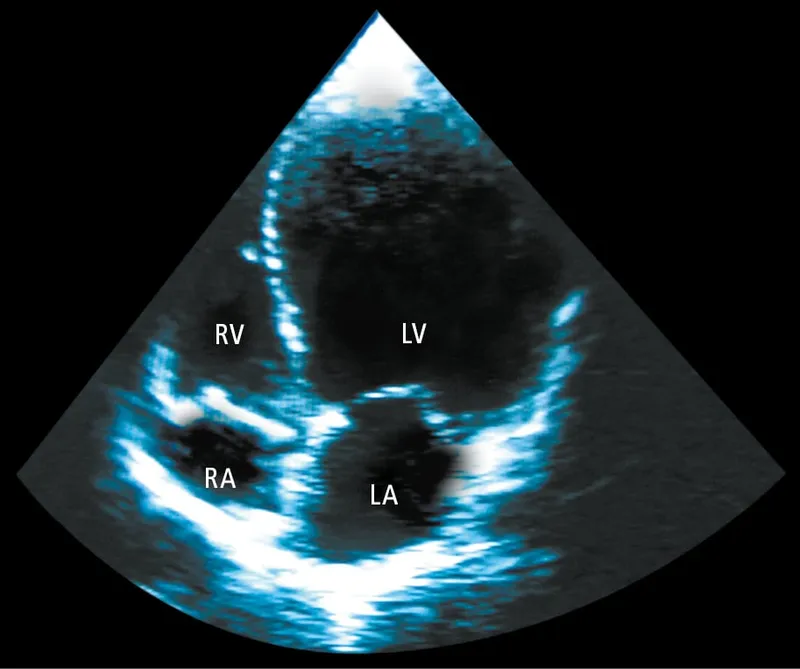

- Dx: Echo (biatrial enlargement, diastolic dysfunction; 'sparkling' myocardium in amyloidosis).

⭐ Amyloidosis is a key cause of RCM, often presenting with a characteristic 'sparkling' appearance on echocardiogram due to amyloid fibril infiltration in the myocardium. Kussmaul's sign is also a classic finding in RCM due to the stiff, non-compliant right ventricle.